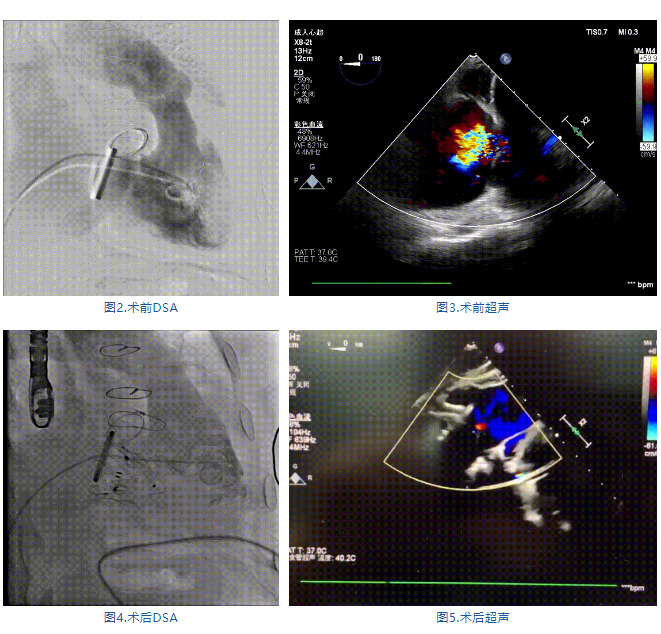

手術在全麻狀態下進行,郭惠明教授團隊采用經右側頸靜脈入路的方式送入輸送器進入體內,并在TEE和DSA的指引下進行。在輸送器進入右室后釋放室間隔錨定裝置,旋轉輸送器,使得錨定裝置對準室間隔面;而后釋放前瓣夾持件,確定夾持件位于右室側釋放LuX-Valve Plus人工瓣膜盤片,再使用DSA和超聲確認盤片是否位于右房側,同時調整瓣膜的同軸性。緊接著在DSA和超聲的監視下調整室間隔錨定件貼合室間隔,釋放室間隔錨定裝置。再次確認瓣膜的穩定性和同軸性后,將輸送器撤出體內,最終完成LuX-Valve Plus人工瓣膜植入(圖2-5),手術獲得圓滿成功。患者在手術室即刻拔除氣管插管,術后超聲提示LuX-Valve Plus人工三尖瓣瓣膜同軸性良好,瓣架固定牢靠,無反流和瓣周漏。